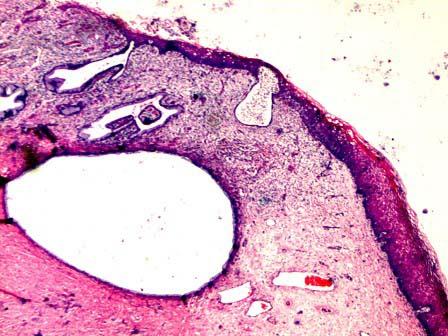

问题 30岁,白带量多,宫颈见多个腺体开口,可见囊肿,取宫颈组织送检,显微镜下所见如图,最适合的诊断为 ( )

选项 A.宫颈鳞状上皮化生 B.宫颈肠上皮化生 C.宫颈纳氏囊肿 D.鳞状上皮包涵囊肿 E.腺瘤样增生

答案 C